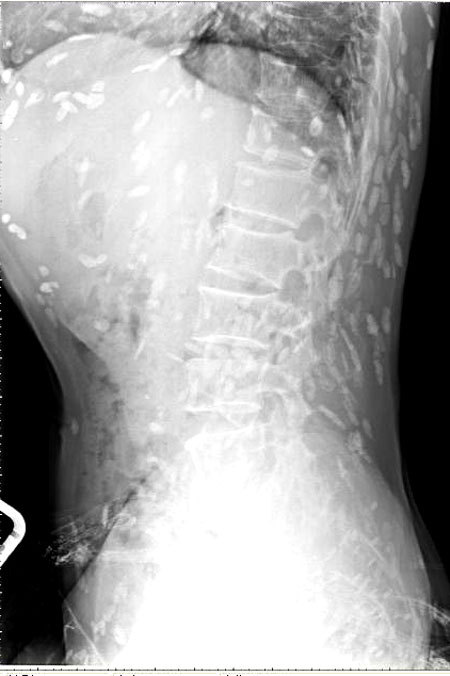

엑스레이를 찍어보니, 온몸에 촌충 같은 기생충이 퍼져있는 것이 Xray사진에 찍혔다.

이 기생충들은 촌충 또는 열두 조충이라는 기생충인데 사람 신체에 침입해 장내에 기생하는 벌레들이다.

익히지 않은 날생선, 쇠고기, 돼지고기를 섭치 하다가 감염되는 경우가 많다.